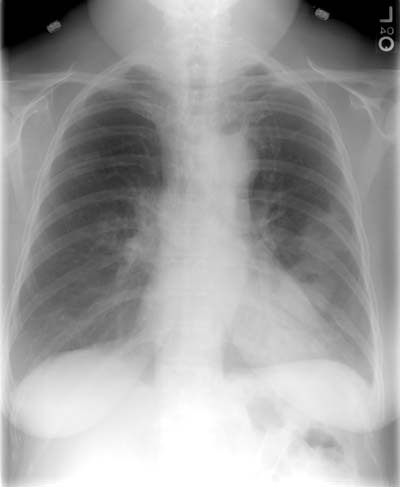

Nocardia Pulmonary Infection- Case 2

The patient was receiving high doses of corticosteroids when the developed symptoms of

pulmonary infection. Multiple, thick walled cavitary nodules can be seen. Bronchoscopy was

performed and cultures grew Nocardia. CXR and CT scan are shown below.